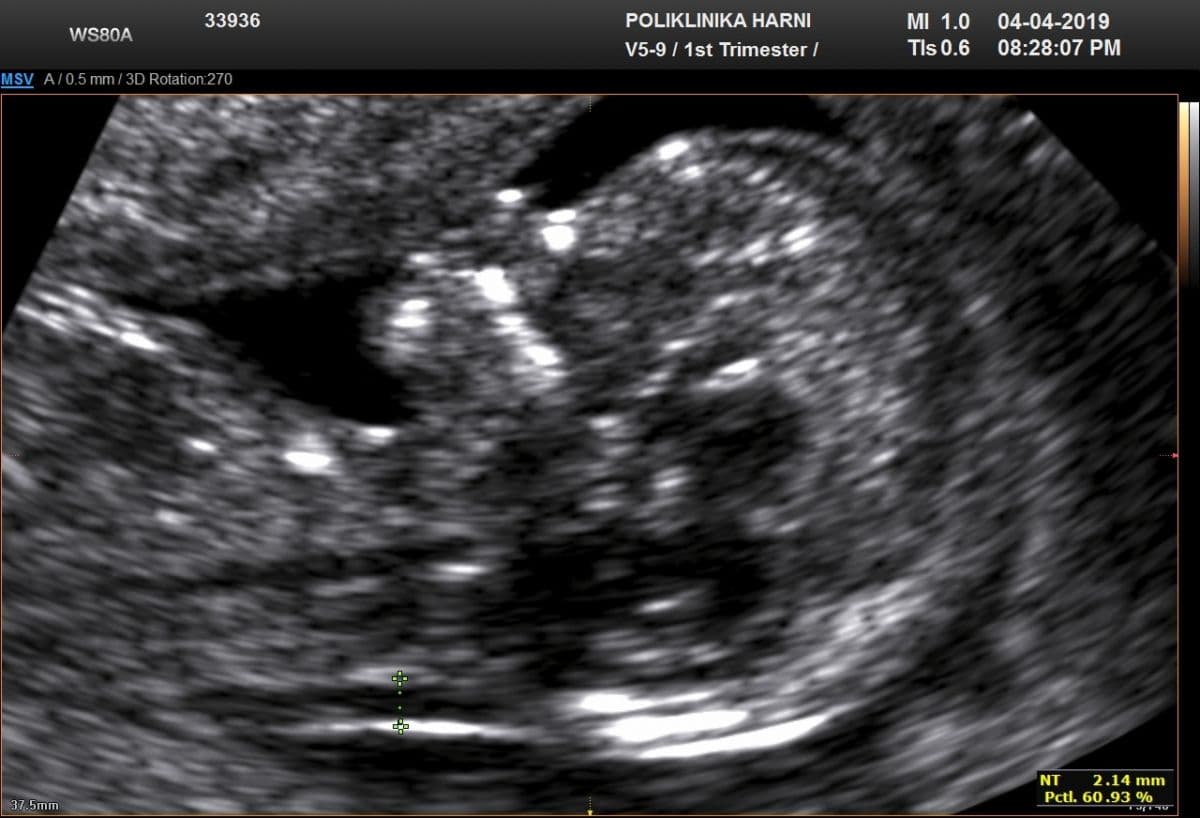

Ultrazvučni pregled u razdoblju između 11. - 14. tjedna trudnoće, poglavito u trudnica koje su prema rezultatima kombiniranog probira svrstane u tzv. skupinu umjerenog rizika za Downov sindrom uključuje i tzv. "dodatne" ultrazvučne biljege:

- mjerenje nosne kosti,

- mjerenje fronto-maksilarnog ličnog kuta,

- mjerenje protoka tijekom atrijske kontrakcije u duktusu venozusu (obojeni Doppler) i

- registracija protoka kroz trikuspidalnu valvulu.

U ovo vrijeme nosna kost se ne može prikazati kod 60 - 70% fetusa s trisomijom 21, kao i kod 2% kromosomski normalnih fetusa. Slična je i s maksilarnom jezgrom, čija se hipoplazija / short maxilla nalazi kod 25% fetusa s trisomijom 21.